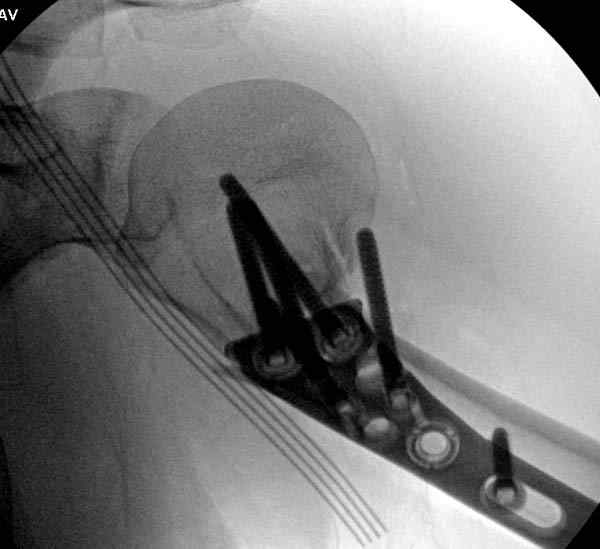

Здесь пример открытой репозиции 57 летнего с переломом плеча (1,2)  смещение обнаружено на  интероперационном снимке. При нормальной прямой проекция (3) угловое смещение обнаружили в аксиальной проекции (4)

После устранения смещения пластина установлена выше (5,6,7) и финальные снимки (8,9,10)